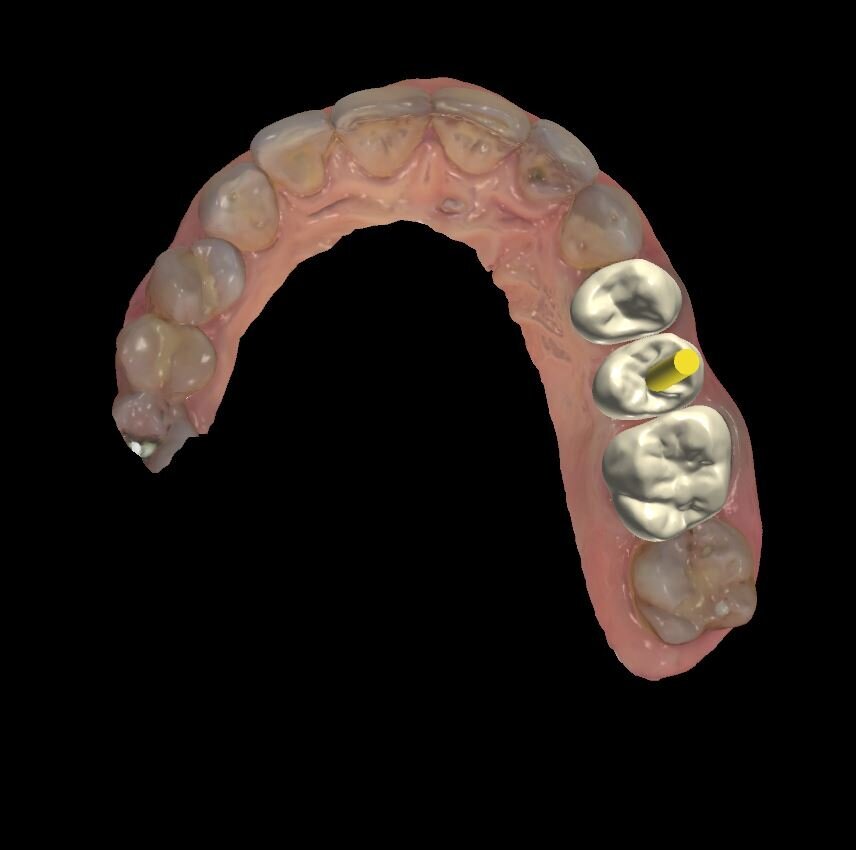

Fig. 3 - Visione occlusale del sito estrattivo nella fase immediatamente successiva la rimozione radicolare.

La paziente di 55 anni, non fumatrice, non affetta da alcuna patologia sistemica, da noi trattata con una procedura implantare sostitutiva dell’elemento naturale si era presentata alla nostra osservazione al fine di poter valutare un dolore riferito in sede 2.5 di tipo continuativo tollerabile ma con scarse variazioni di picco algico. L’elemento era stato curato endodonticamente e protesicamente da meno di 1 anno. All’esame obiettivo si presentava una neo protesizzazione individuale su 2.4 e 2.5, mentre su 2.6 si presentava una pregressa protesizzazione in oro-resina con vistosa retrazione gengivale che scopriva un margine corono-protesico impreciso. Il dolore riferito si estendeva tra i 2 premolari in oggetto. Al sondaggio si evidenziava un tragitto patologico di 9 mm in sede mesio-vestibolare della corona in 2.5 (Fig. 1) mentre il sondaggio degli altri elementi si configurava come fisiologico, privo di sanguinamento. L’esame radiografico endorale, mirato al sito ed eseguito con un centratore evidenziava un baffo medicamentale posto mesialmente e associato ad una lacuna ossea adiacente (Fig. 2). La diagnosi di frattura verticale non consentiva alcun recupero radicolare, mentre le radici adiacenti pur avendo delle diafanie periapicali non presentavano sintomi, al fine di un recupero protesico dell’emiarcata si è preferito eseguire una nuova terapia radicolare endodontica (Fig. 3). Fatta la diagnosi si apre un’attenta valutazione sulla tecnica chirurgica, alcune considerazioni vanno fatte sul tipo di estrazione per riuscire ad essere quanto più conservativi, per il mantenimento della cresta ossea vestibolare e per l’architettura gengivale. In tal caso le tecniche atraumatiche prevedono l’utilizzo di strumenti volti alla percussione estrattiva della radice, o al sezionamento obliquo o all’uso di strumenti ultrasonici che lesionano l’attacco dei legamenti parodontali senza intaccare la struttura ossea. Su quest’ultima è ricaduta la nostra tecnica consentendoci di ottenere un sito pulito da frammenti sia ossei che radicolari e riducendo al minimo le lesioni vascolari, senza lembi d’accesso e con un alveolo esangue.